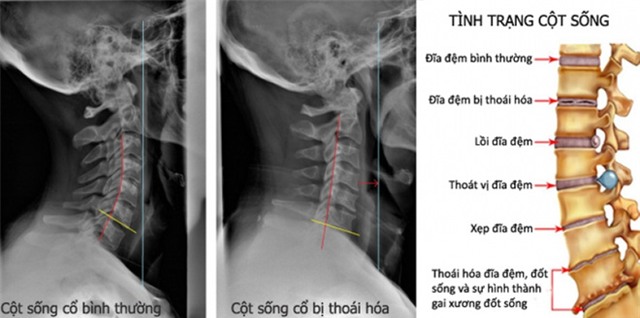

Thoái hóa đốt sống cổ: Căn bệnh biết "đẻ"

Theo các chuyên gia, cổ chính là bộ phận quan trọng hàng đầu trên cơ thể, bởi bệnh thoái hóa đốt sống cổ được xem là căn nguyên sinh ra hàng trăm loại bệnh khác phức tạp hơn.

Các chuyên gia sức khỏe y tế cho rằng, vai trò của đốt sống cổ đối với sức khỏe là vô cùng lớn, nó dễ dàng bị tổn thương trong khi sự quan tâm của con người rất hạn chế.

Đốt sống cổ có tần suất hoạt động cao, gần như không ngừng nghỉ trong hơn 2/3 thời gian của đời người. Vì thế, chúng lại càng chịu sức ép lớn giống như việc liên tục lao động quá sức.

Các chuyên gia xương khớp cho biết bệnh thoái hóa đốt sống cổ có 5 loại chính, bao gồm cố định xương cổ, rễ thần kinh, tủy sống, thần kinh giao cảm, động mạch xoay chuyển.

Trong đó, căn bệnh dễ bị mắc nhất chính là đau rễ thần kinh cổ chiếm 60-70% tỉ lệ bệnh nhân mắc bệnh về thoái hóa đốt sống cổ.